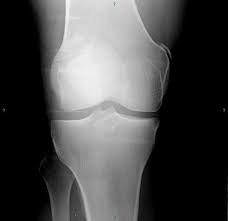

The radiographs demonstrated abnormal contour of the medial femoral condyle, consistent with an osteochondral defect, and a fabella posterior to the knee.

Medial condyle of femur from wikipedia, the free encyclopedia the medial condyle is one of the two projections on the lower extremity of femur, the other being the lateral condyle. The lateral condyle was involved in 44 % and the medial condyle in 12 %. Palpable as a hard, rounded bump to the inside of either knee joint, they are one of two condyles at the bottom of each leg bone, the other being the lateral femoral condyle. This adaptable graft option is most commonly used with oats or shell techniques to restore cartilage in the knee, but can also be used to for cartilage restoration of other joints. In a review of 79 patients with this disease, performed to establish guidelines f … The medial femoral condyle is supplied by a plexus of vessels from the descending genicular artery and the medial superior genicular artery. The medial condyle is larger than the lateral (outer) condyle due to more weight bearing caused by the centre of mass being medial to the knee. Root tear (radial tear) of the medial meniscus mild or moderate knee arthritis According to the hospital for special surgery, the medial femoral condyle is the inside of the knee, and health issues dealing with it can be treated. Osteonecrosis of the medial femoral condyle can be treated in a variety of ways depending on the stage of the disease. The medial condyle is named for its location on the inside of the knee, closer to the midline of the body, while the lateral condyle is found on the outside of the knee, away from the midline of the body. In the knee, chondromalacia is usually related to injury, overuse of the knee, and poorly aligned muscles and bones around the knee joint. Your knee mri will often show a:

Of the six patients who had suffered an isolated fracture of their medial condyle, four of the patients had their fractures diagnosed on the first visit. The lateral condyle was involved in 44 % and the medial condyle in 12 %. It acts to support a significant amount of the patient's body weight. Cartilage can be focally damaged, producing a pot hole in the joint surface, when the knee ligaments are injured. Osteonecrosis of the medial femoral condyle presents as a sudden onset of pain on the medial side of the knee. A bone fracture at this location is termed a femoral condyle fracture. The femoral condyle is a thickened area of the femur just above the knee. One presumed mechanism of injury is a stieda fracture (avulsion injury of the medial collateral ligament at the medial femoral condyle). Root tear (radial tear) of the medial meniscus mild or moderate knee arthritis Coronal plane fracture of the lateral femoral condyle. The lesions were located on the medial femoral condyle in 8 (72.7%) cases and on the medial tibial plateau in 3 cases (27.3%). The medial femoral condyles are the bony protrusions on the inside edge of the bottom of the femur bone in each thigh. Based on the patient's antalgic gait and radiographic findings, the patient was instructed on the proper use of crutches and referred to an orthopaedic surgeon for appropriate management.